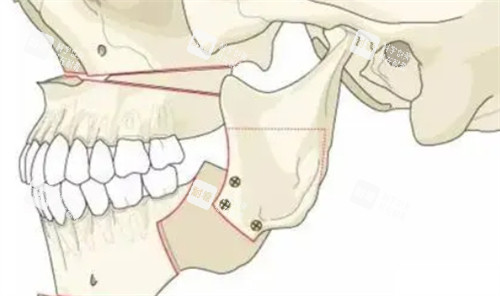

這些逆襲病例背后,是周會(huì)喜團(tuán)隊(duì)20年磨一劍的“硬核技術(shù)”。作為南方醫(yī)學(xué)大學(xué)口腔頜面外科主管醫(yī)師、廣東省整形美容團(tuán)隊(duì)理事,他手里的“家伙事兒”可不止手術(shù)刀——CT影像+3D打印導(dǎo)板,能把頜骨截骨誤差控制在0.1毫米內(nèi),“就像給骨頭裝了個(gè)GPS,避開(kāi)神經(jīng)血管,連‘歪嘴’都能精細(xì)復(fù)位!”

傳統(tǒng)正頜手術(shù)要在臉上開(kāi)外部切口,插引流管,術(shù)后腫得像“發(fā)面饅頭”,改善期長(zhǎng)達(dá)3個(gè)月。但周會(huì)喜團(tuán)隊(duì)用口內(nèi)切口+超聲電刀剝離組織,出血量不到傳統(tǒng)手術(shù)的1/5,“術(shù)后不用插管,腫脹期縮短到1-2周,堪稱‘午休式手術(shù)’!”更絕的是,他不僅修復(fù)咬合功能,還會(huì)根據(jù)五官比例設(shè)計(jì)頜骨形態(tài)——“月亮臉”求美者,他會(huì)增加下頜角寬度,告別“錐子臉違和感”;“大小臉”求美者,通過(guò)骨縫調(diào)整,讓左右臉對(duì)稱度堪比3D打印。